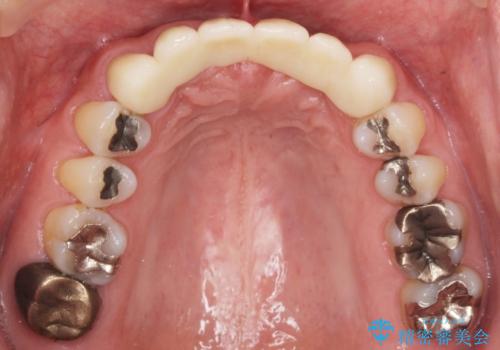

- お風呂場で転んで上の前歯が2本抜けてしまったことを主訴に来院された患者様です。

精査したところ、左上の側切歯(左上2)も破折しており保存不可能な状態でした。

左上の側切歯(左上2)を抜去し、右上の側切歯(右上2)の再根管治療後、セラミックのブリッジによる補綴を行いました。